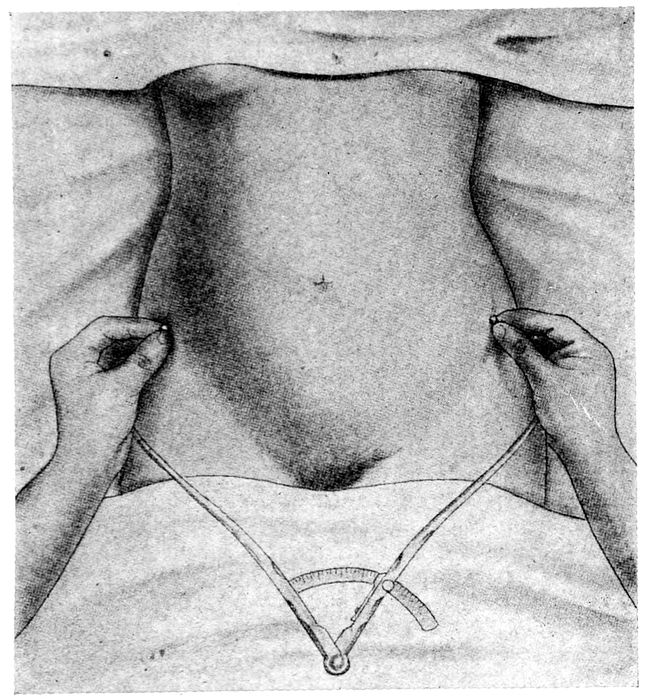

| 94. |

The pelvimeter |

216 |

| |

| 95. |

The various diameters of the inlet |

216 |

| |

| 96. |

Measuring the distance between the anterior superior spines of the pelvis |

217 |

| |

| 97. |

Measuring the external conjugate |

218 |

| |

| 98. |

Measuring the diagonal conjugate with the finger |

219 |

| |